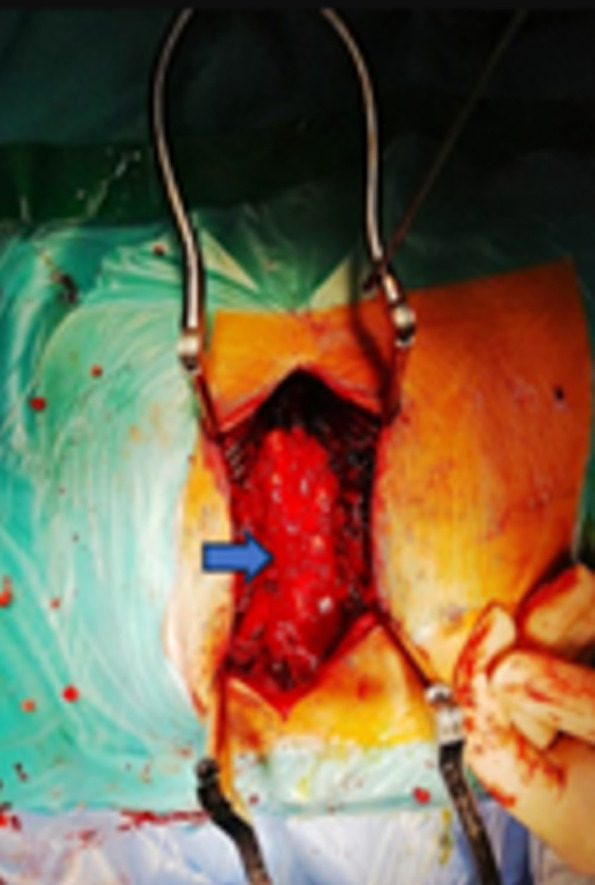

硬膜外海绵状血管瘤是一种罕见的血管畸形,占所有脊髓血管畸形的5-12%。我们报告一例由于海绵状血管瘤模仿沙漏形硬膜外神经瘤的临床和放射学特征而导致的D5-D6低位脊髓压迫。临床表现为进行性痉挛性截瘫超过6个月,患者41岁,无明显病史。磁共振成像显示D5-D6硬膜内压缩病变伴T2高信号,呈沙漏状,提示硬膜外神经瘤,伴显著的肛门外成分填充同侧椎体外侧间隙。免疫组化组织学检查证实为海绵状血管瘤。手术切除病灶后,术后结果良好。

Epidural cavernous hemangioma is a rare vascular malformation, accounting for 5-12% of all spinal cord vascular malformations. We report a case of low dorsal spinal cord compression at D5-D6 due to a cavernous hemangioma mimicking the clinical and radiological features of an epidural neuroma in an hourglass shape. The clinical presentation was progressive spastic paraplegia over six months in a 41-year-old patient with no significant medical history. Magnetic resonance imaging showed a compressive D5-D6 intradural lesion with T2 hyperintensity, displaying an hourglass appearance suggestive of an epidural neuroma, with a significant extracanal component filling the ipsilateral latero-vertebral space. Histological examination confirmed cavernous hemangioma by immunohistochemistry. The postoperative outcome was favorable following total surgical removal of the lesion.